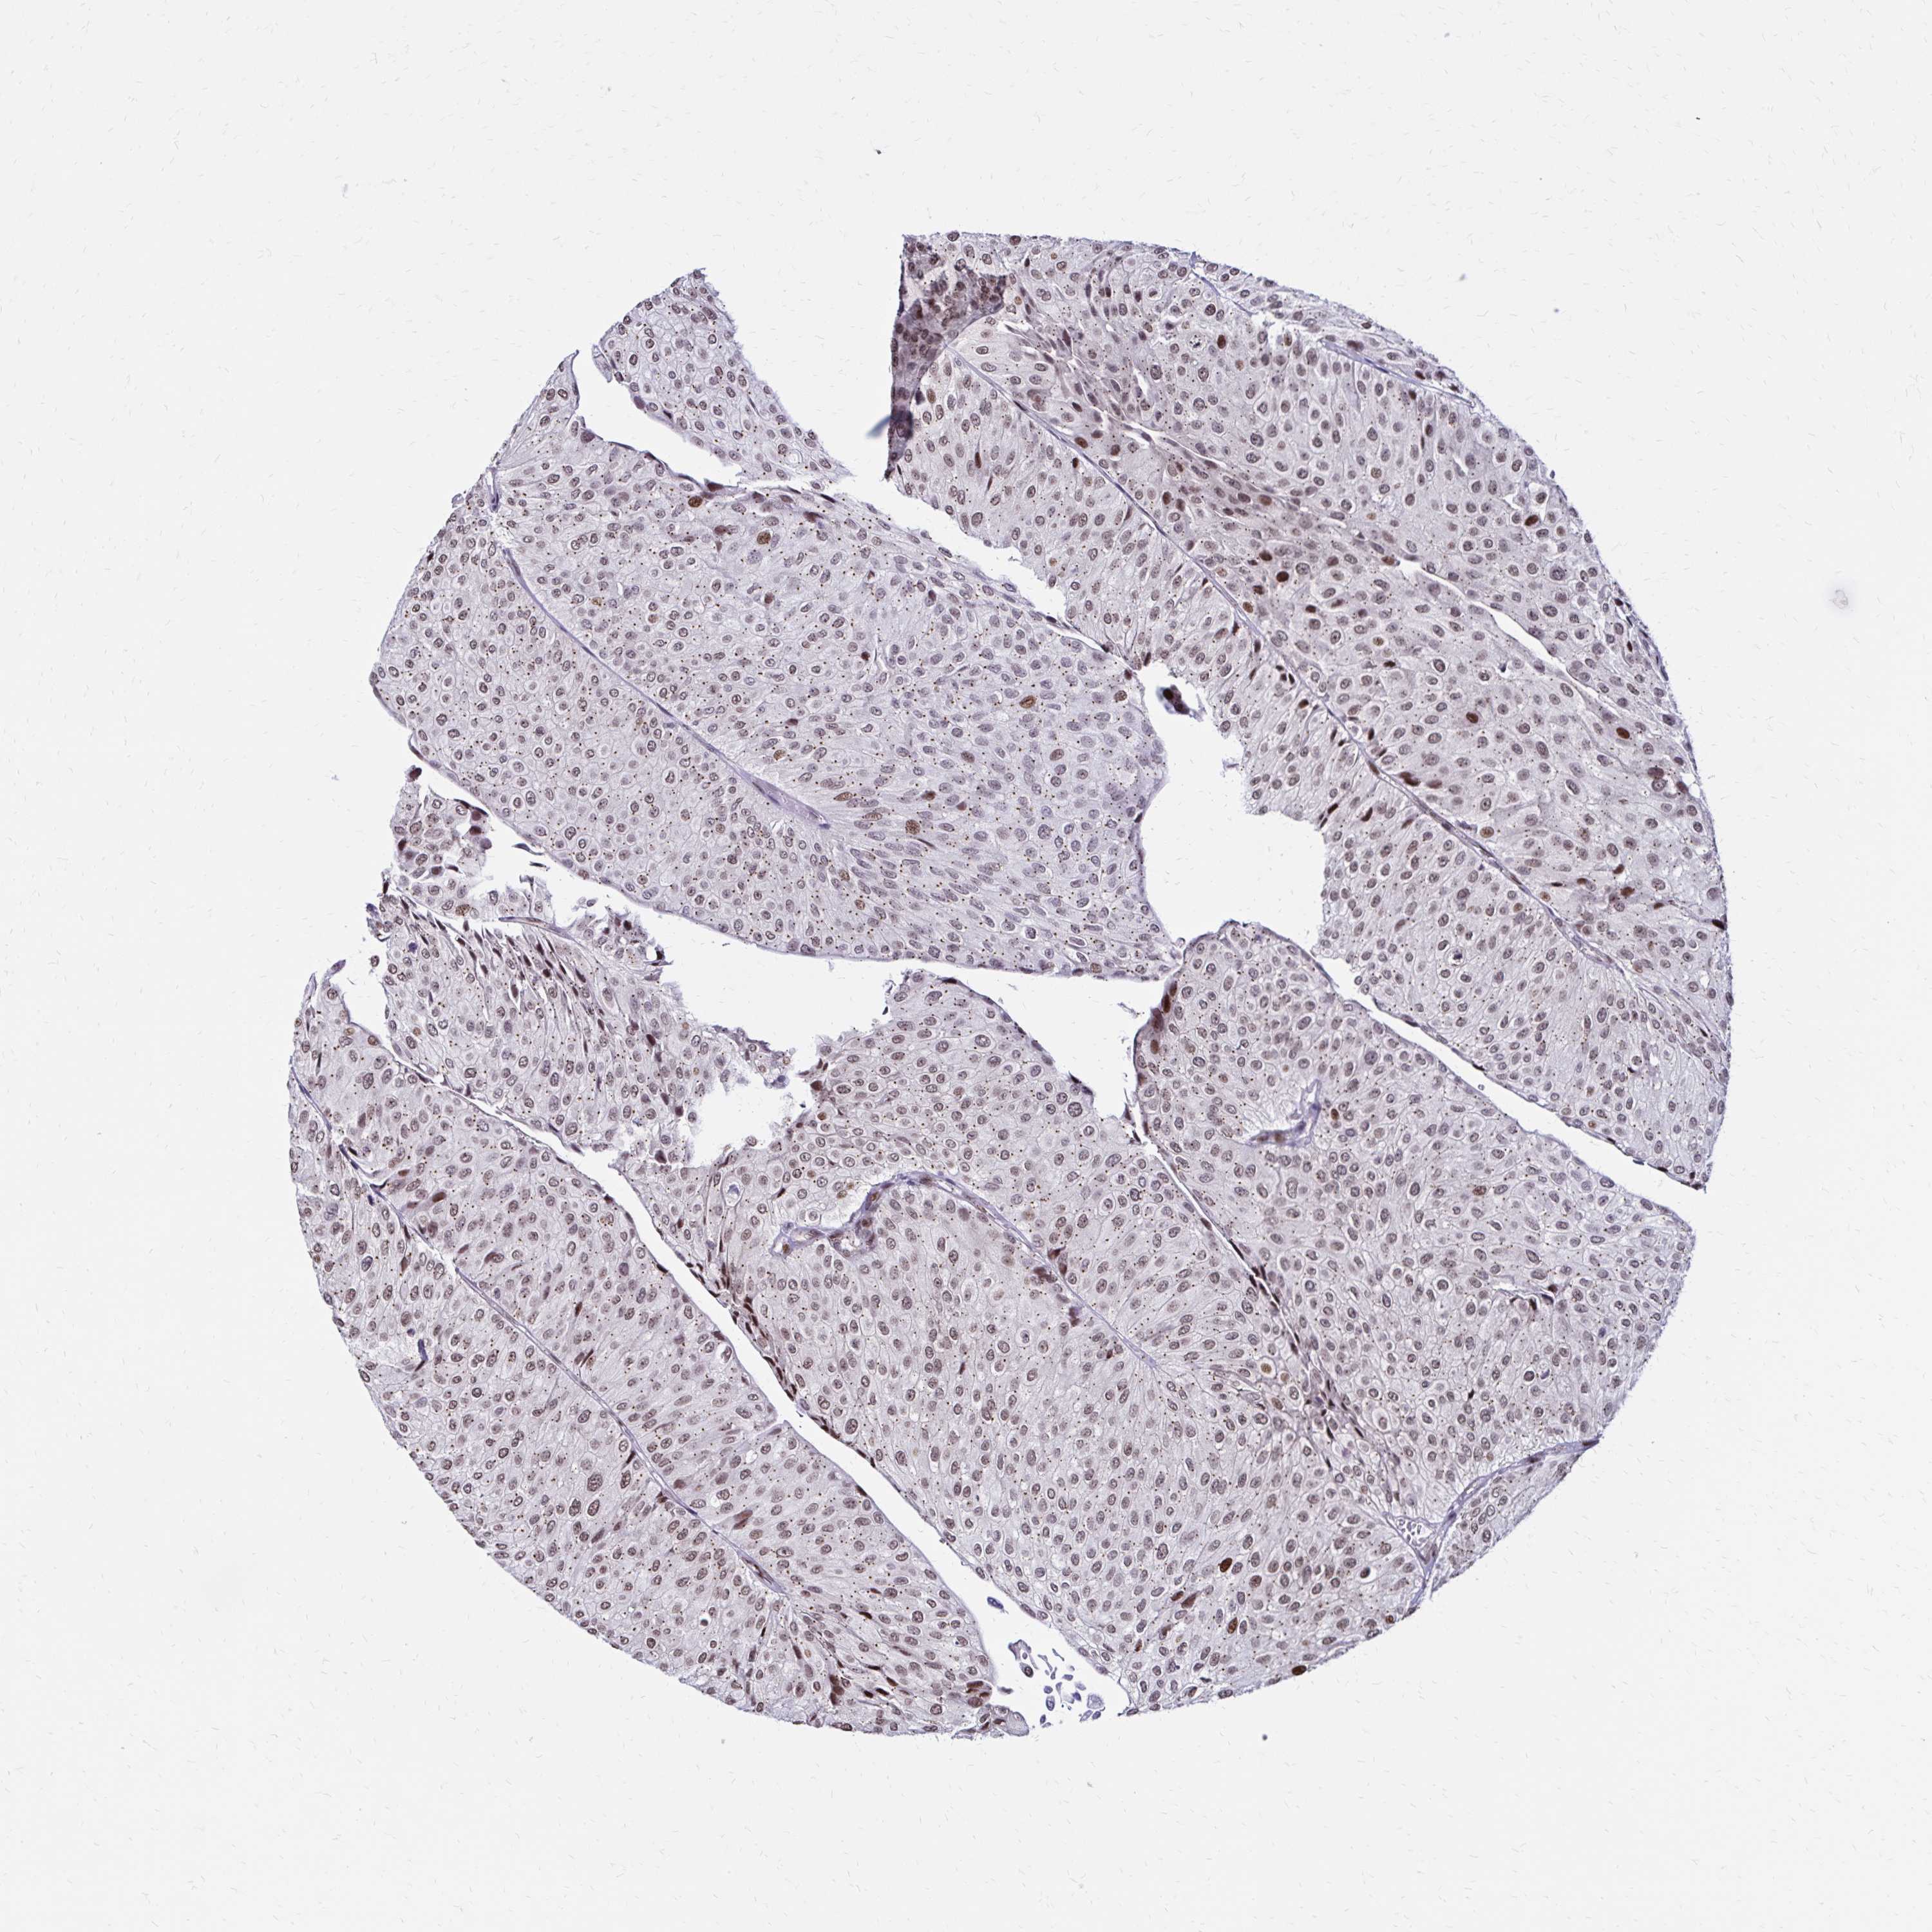

UROTHELIAL CANCER - Protein expressioni

A mouse-over function shows sample information and annotation data. Click on an image to view it in a full screen mode. Samples can be filtered based on level of antibody staining by selecting one or several of the following categories: high, medium, low and not detected. The assay and annotation is described here.

Note that samples used for immunohistochemistry by the Human Protein Atlas do not correspond to samples in the TCGA dataset.

Antibody stainingi

Antibody staining in the annotated cell types in the current human tissue is reported as not detected, low, medium, or high, based on conventional immunohistochemistry profiling in selected tissues. This score is based on the combination of the staining intensity and fraction of stained cells.

Each image is clickable and will lead to virtual microscopy that enables deeper exploration of all samples and also displays staining intensity scores, fraction scores and subcellular localization as well as patient and tissue information for each sample.

Antibody HPA047839

Staining

High

Medium

Low

Not detected

Intensity

Strong

Moderate

Weak

Negative

Quantity

>75%

75%-25%

<25%

None

Location

Nuclear

Cytoplasmic/membranous

Cytoplasmic/membranous,nuclear

Urothelial carcinoma, High grade

Urothelial carcinoma, Low grade

Urothelial carcinoma, NOS